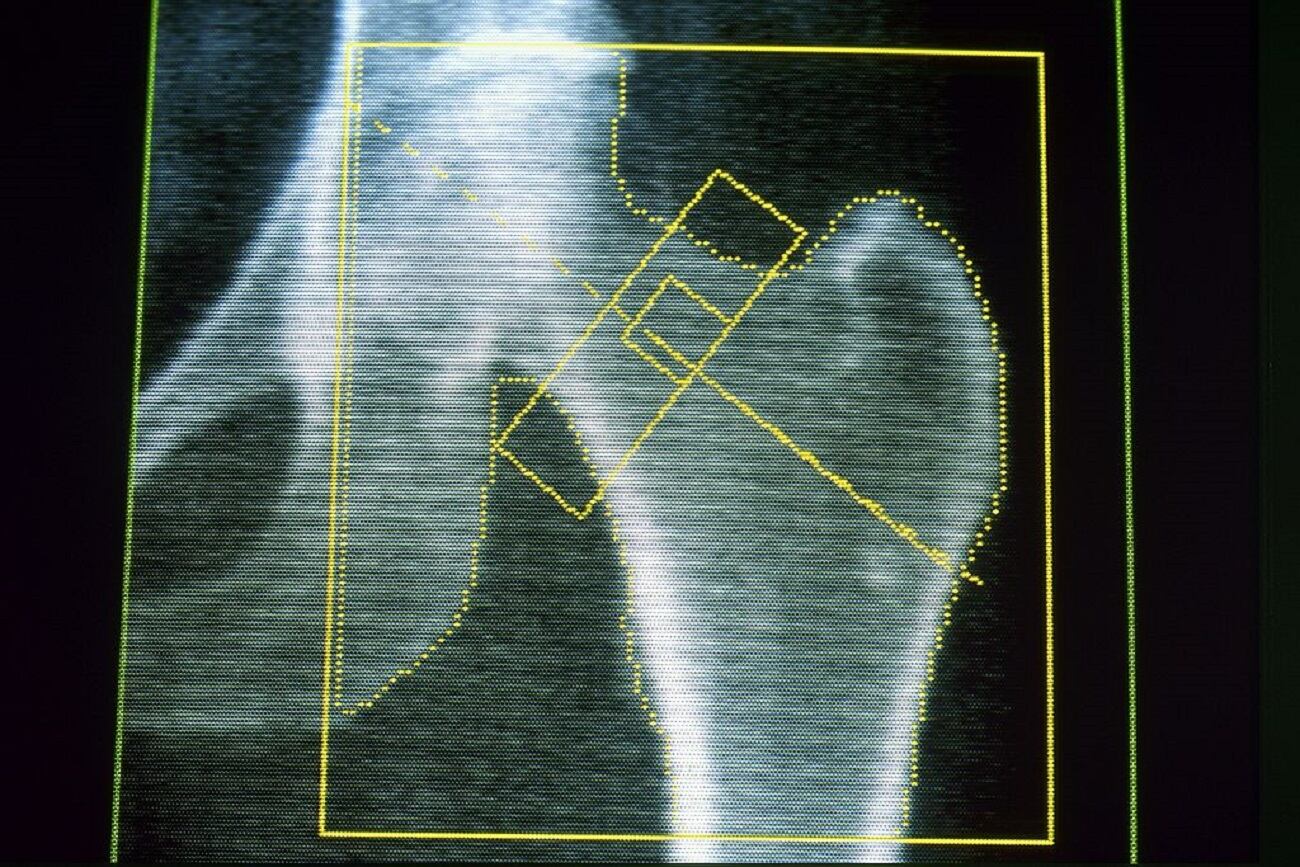

Algunos signos de la osteoporosis, como el adelgazamiento de la columna inferior, el cuello femoral y la cadera son especialmente predictivos de un mayor riesgo de ataque cardíaco y accidente cerebrovascular.